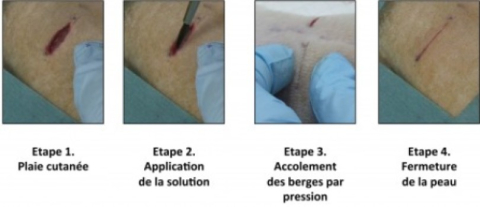

Унікальна розробка дозволить медикам не зашивати, а склеювати рани

Нове відкриття медиків може викликати переворот у хірургії та регенеративній медицині: дослідники виявили, що рани можна не зашивати, а склеювати. Зчеплення м’яких тканин виконується за принципом адгезії наночасток — такий тип склеювання широко застосовується...2015-09-16T19:11:00 -